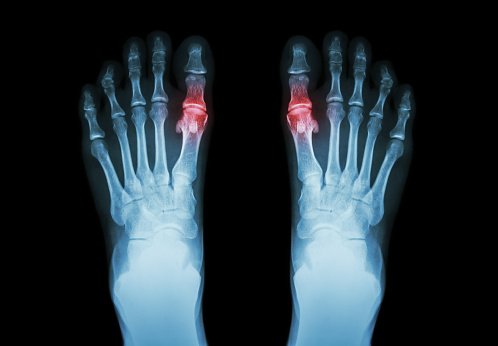

En este estudio retrospectivo de pacientes con antecedentes de gota, los niveles de urato sérico al inicio del estudio se asociaron con el riesgo de brotes de gota posteriores y las tasas de hospitalización por gota recurrente. Estos hallazgos respaldan el uso de un nivel inicial de urato sérico para evaluar el riesgo de gota recurrente durante casi 10 años de seguimiento. JAMA, 6 de febrero de 2024.